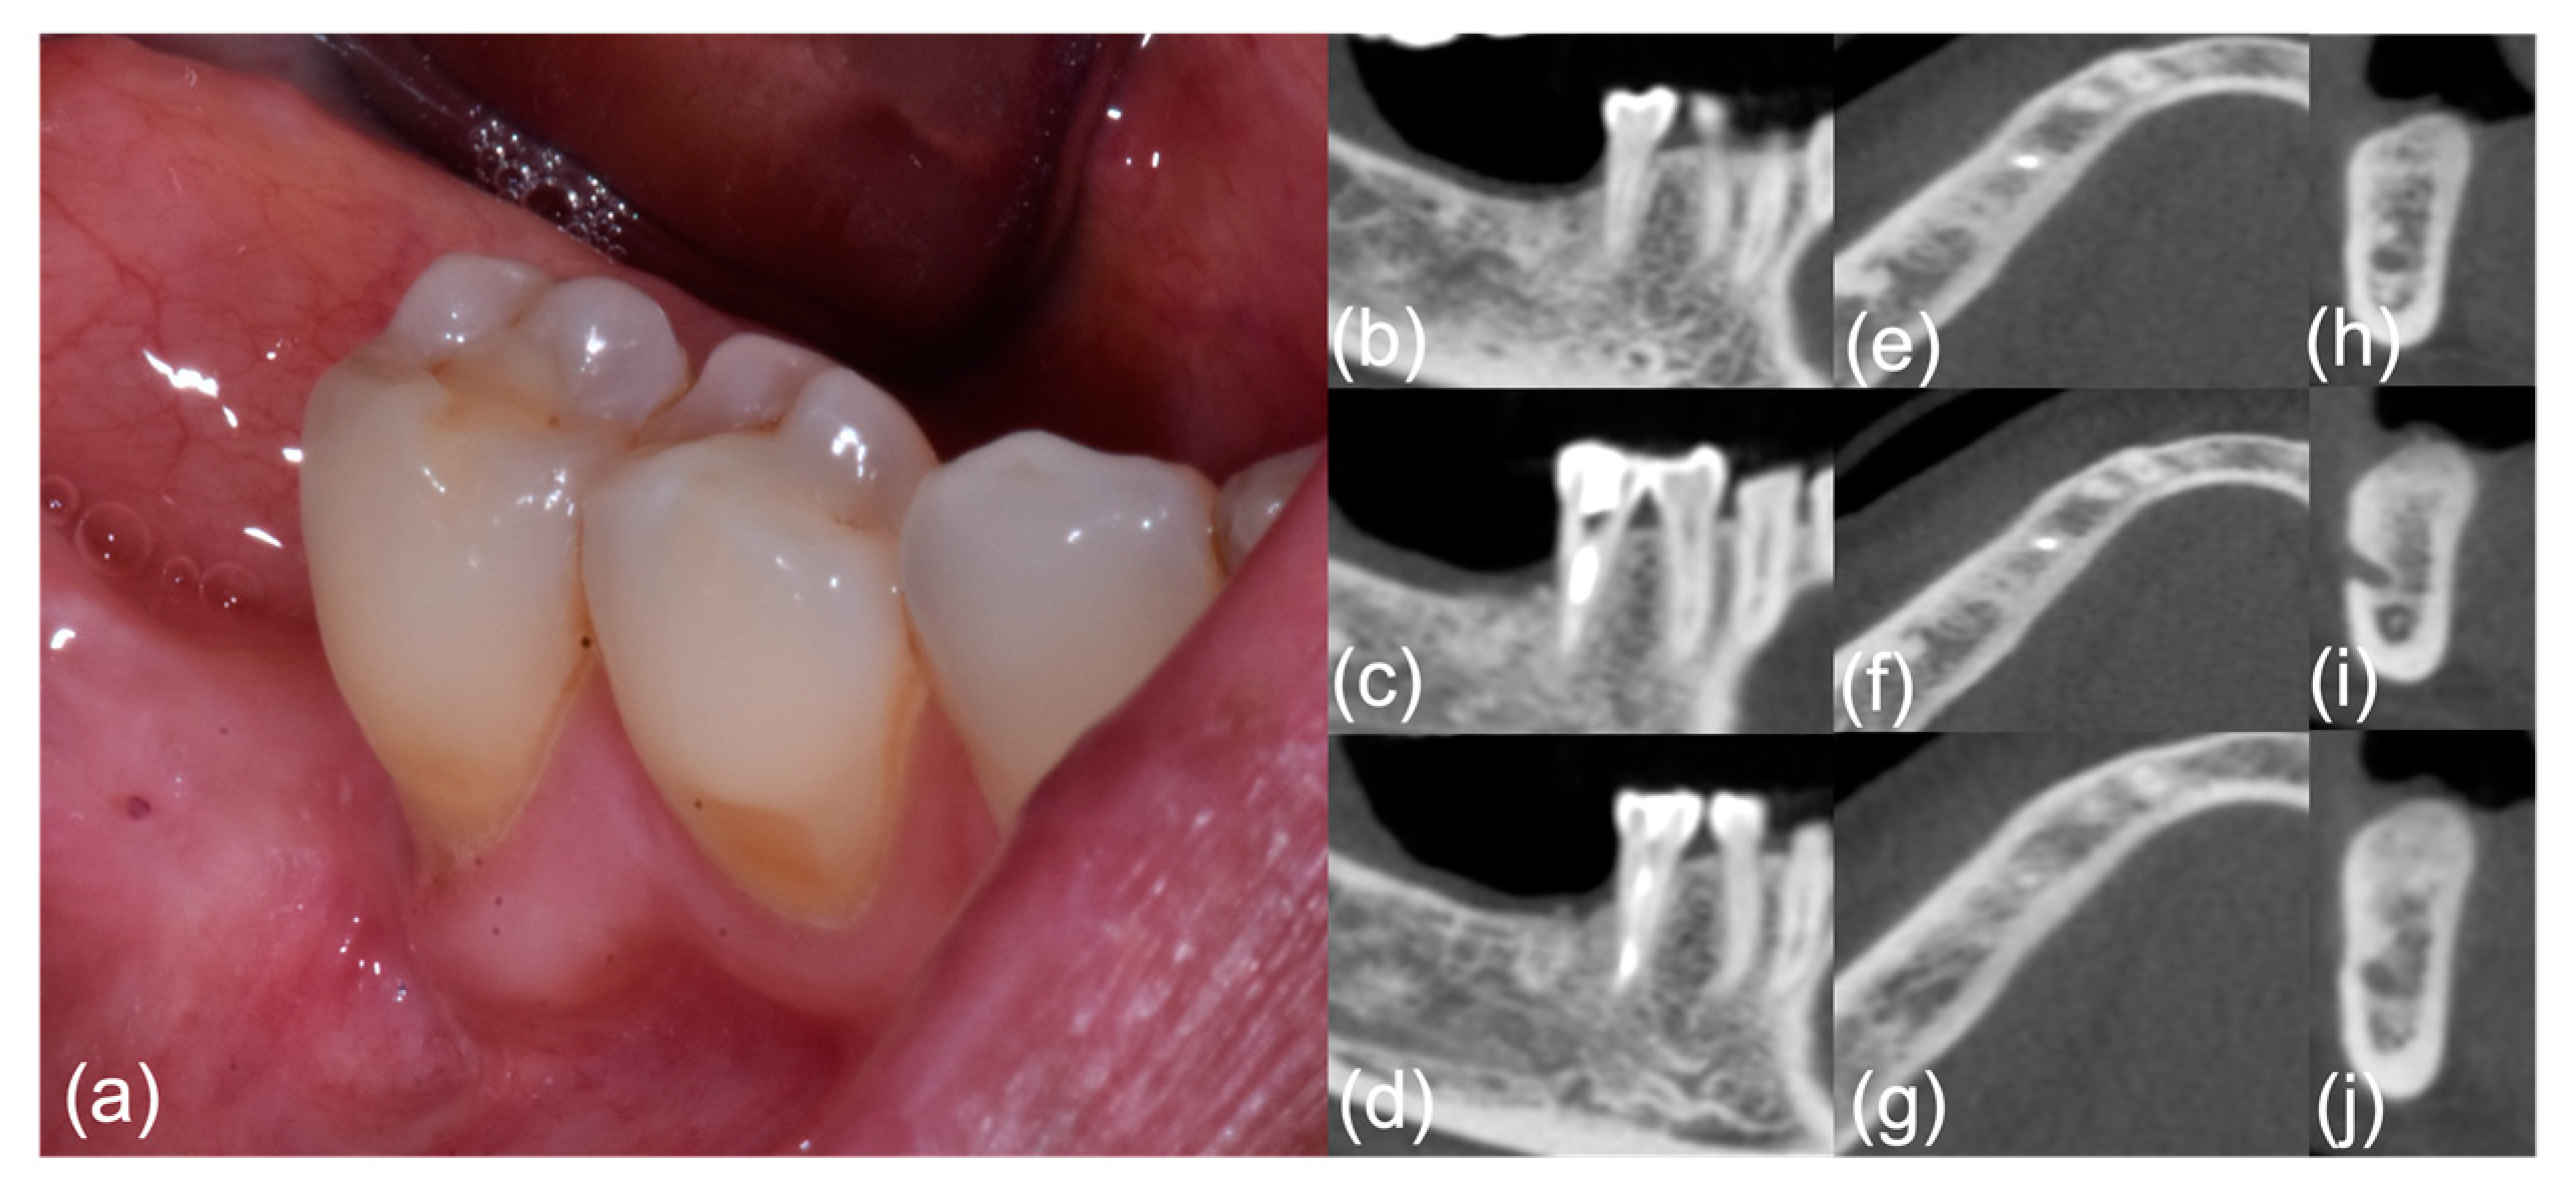

| #1 | E Pu P | 8 | II | Ground glass disappearance (improvement) | No pain/no ONJ signs | n.a. | n.a. |

| #2 | E Pu P | 7 | II | Bone healing (improvement) | No pain/no ONJ signs | Stable (improvement) | No pain/no ONJ signs |

| #3 | Pu S Pa P | 10 | II | Slightly improved bone formation with persistent ground glass (improvement) | No pain/no ONJ signs | Bone formation (improvement) | No pain/no ONJ signs |

| #4 | A E P | 10 | II | Slightly improved bone formation (improvement) | No pain/no ONJ signs | Periosteal reaction (improvement) | No pain/no ONJ signs |

| #5 | F E P | 7 | II | Slightly improved bone formation (improvement) | No pain/no ONJ signs | Stable (improvement) | No pain/no ONJ signs |

| #6 | De E P | 6 | II | Slightly improved bone formation (improvement) | No pain/no ONJ signs | Stable (improvement) | No pain/no ONJ signs |

| #7 | F E D | 7 | II | Slightly improved bone formation (improvement) | No pain/no ONJ signs | n.a. | n.a. |